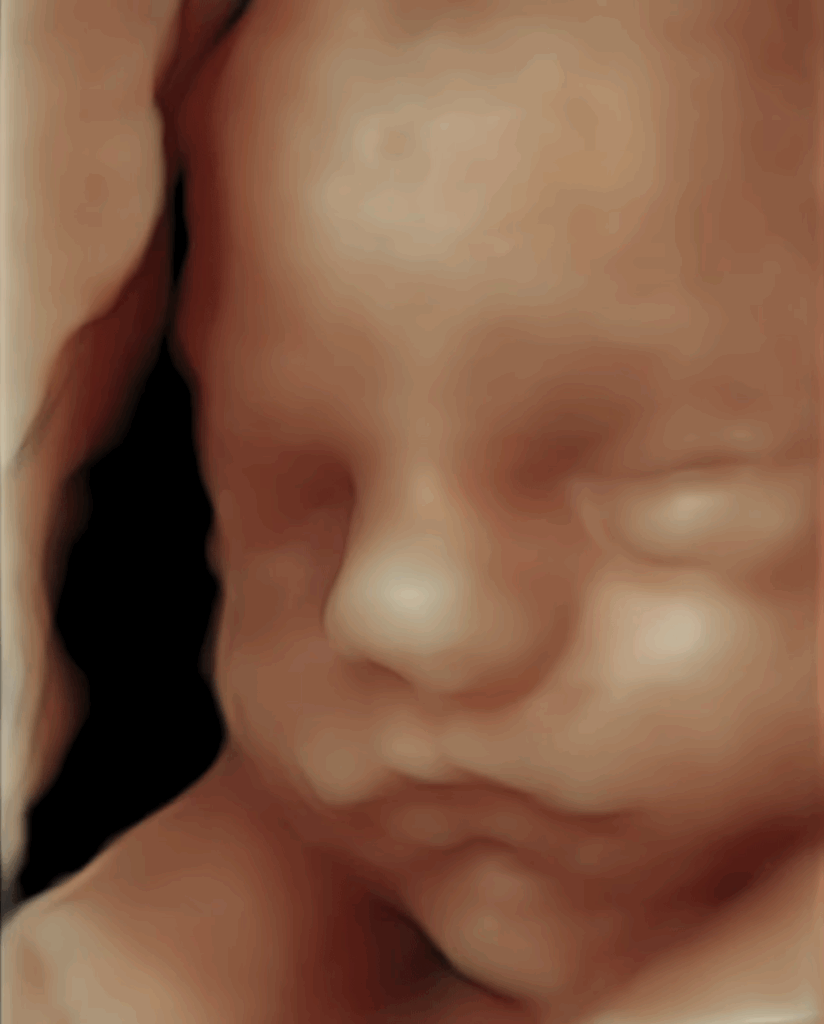

목투명대(Nuchal Translucency, NT) 관찰

임신 초기에는 태아 목 뒤 투명층의 두께를 관찰하여 염색체 이상 위험도를 평가합니다.

정확한 단면에서 측정하며, 필요 시 추가 검사에 대해 설명드립니다.